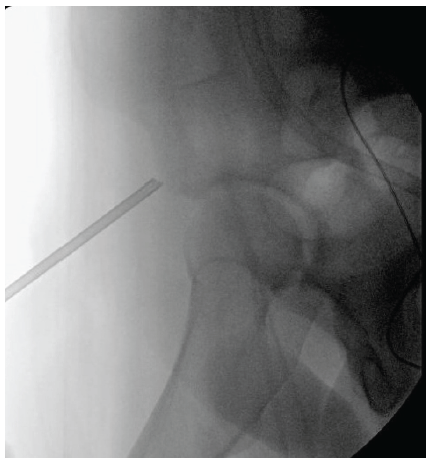

Next, fluoroscopy was used to identify the anterior inferior iliac spine (AIIS) and the AIIS footprint was prepared by removing residual fascial attachments and using a cobb elevator to create a bleeding bone surface. An obturator outlet view was utilized to confirm placement in the supracetabular bone and an iliac oblique view was used to direct anchors superior to the acetabulum. A 2.6 mm Fibertak (Arthrex) triple-loaded anchor was placed into the footprint with excellent fixation (Fig. 5), and a free needle was used to run 2 of the sutures through the tendon in a Krakow manner and the 3rd more distally as a rip-stop suture (Fig. 6).

Figure 5: Intraoperative fluoroscopy showing insertion of 2.6 mm Fibertak directed into the anterior inferior iliac spine footprint.